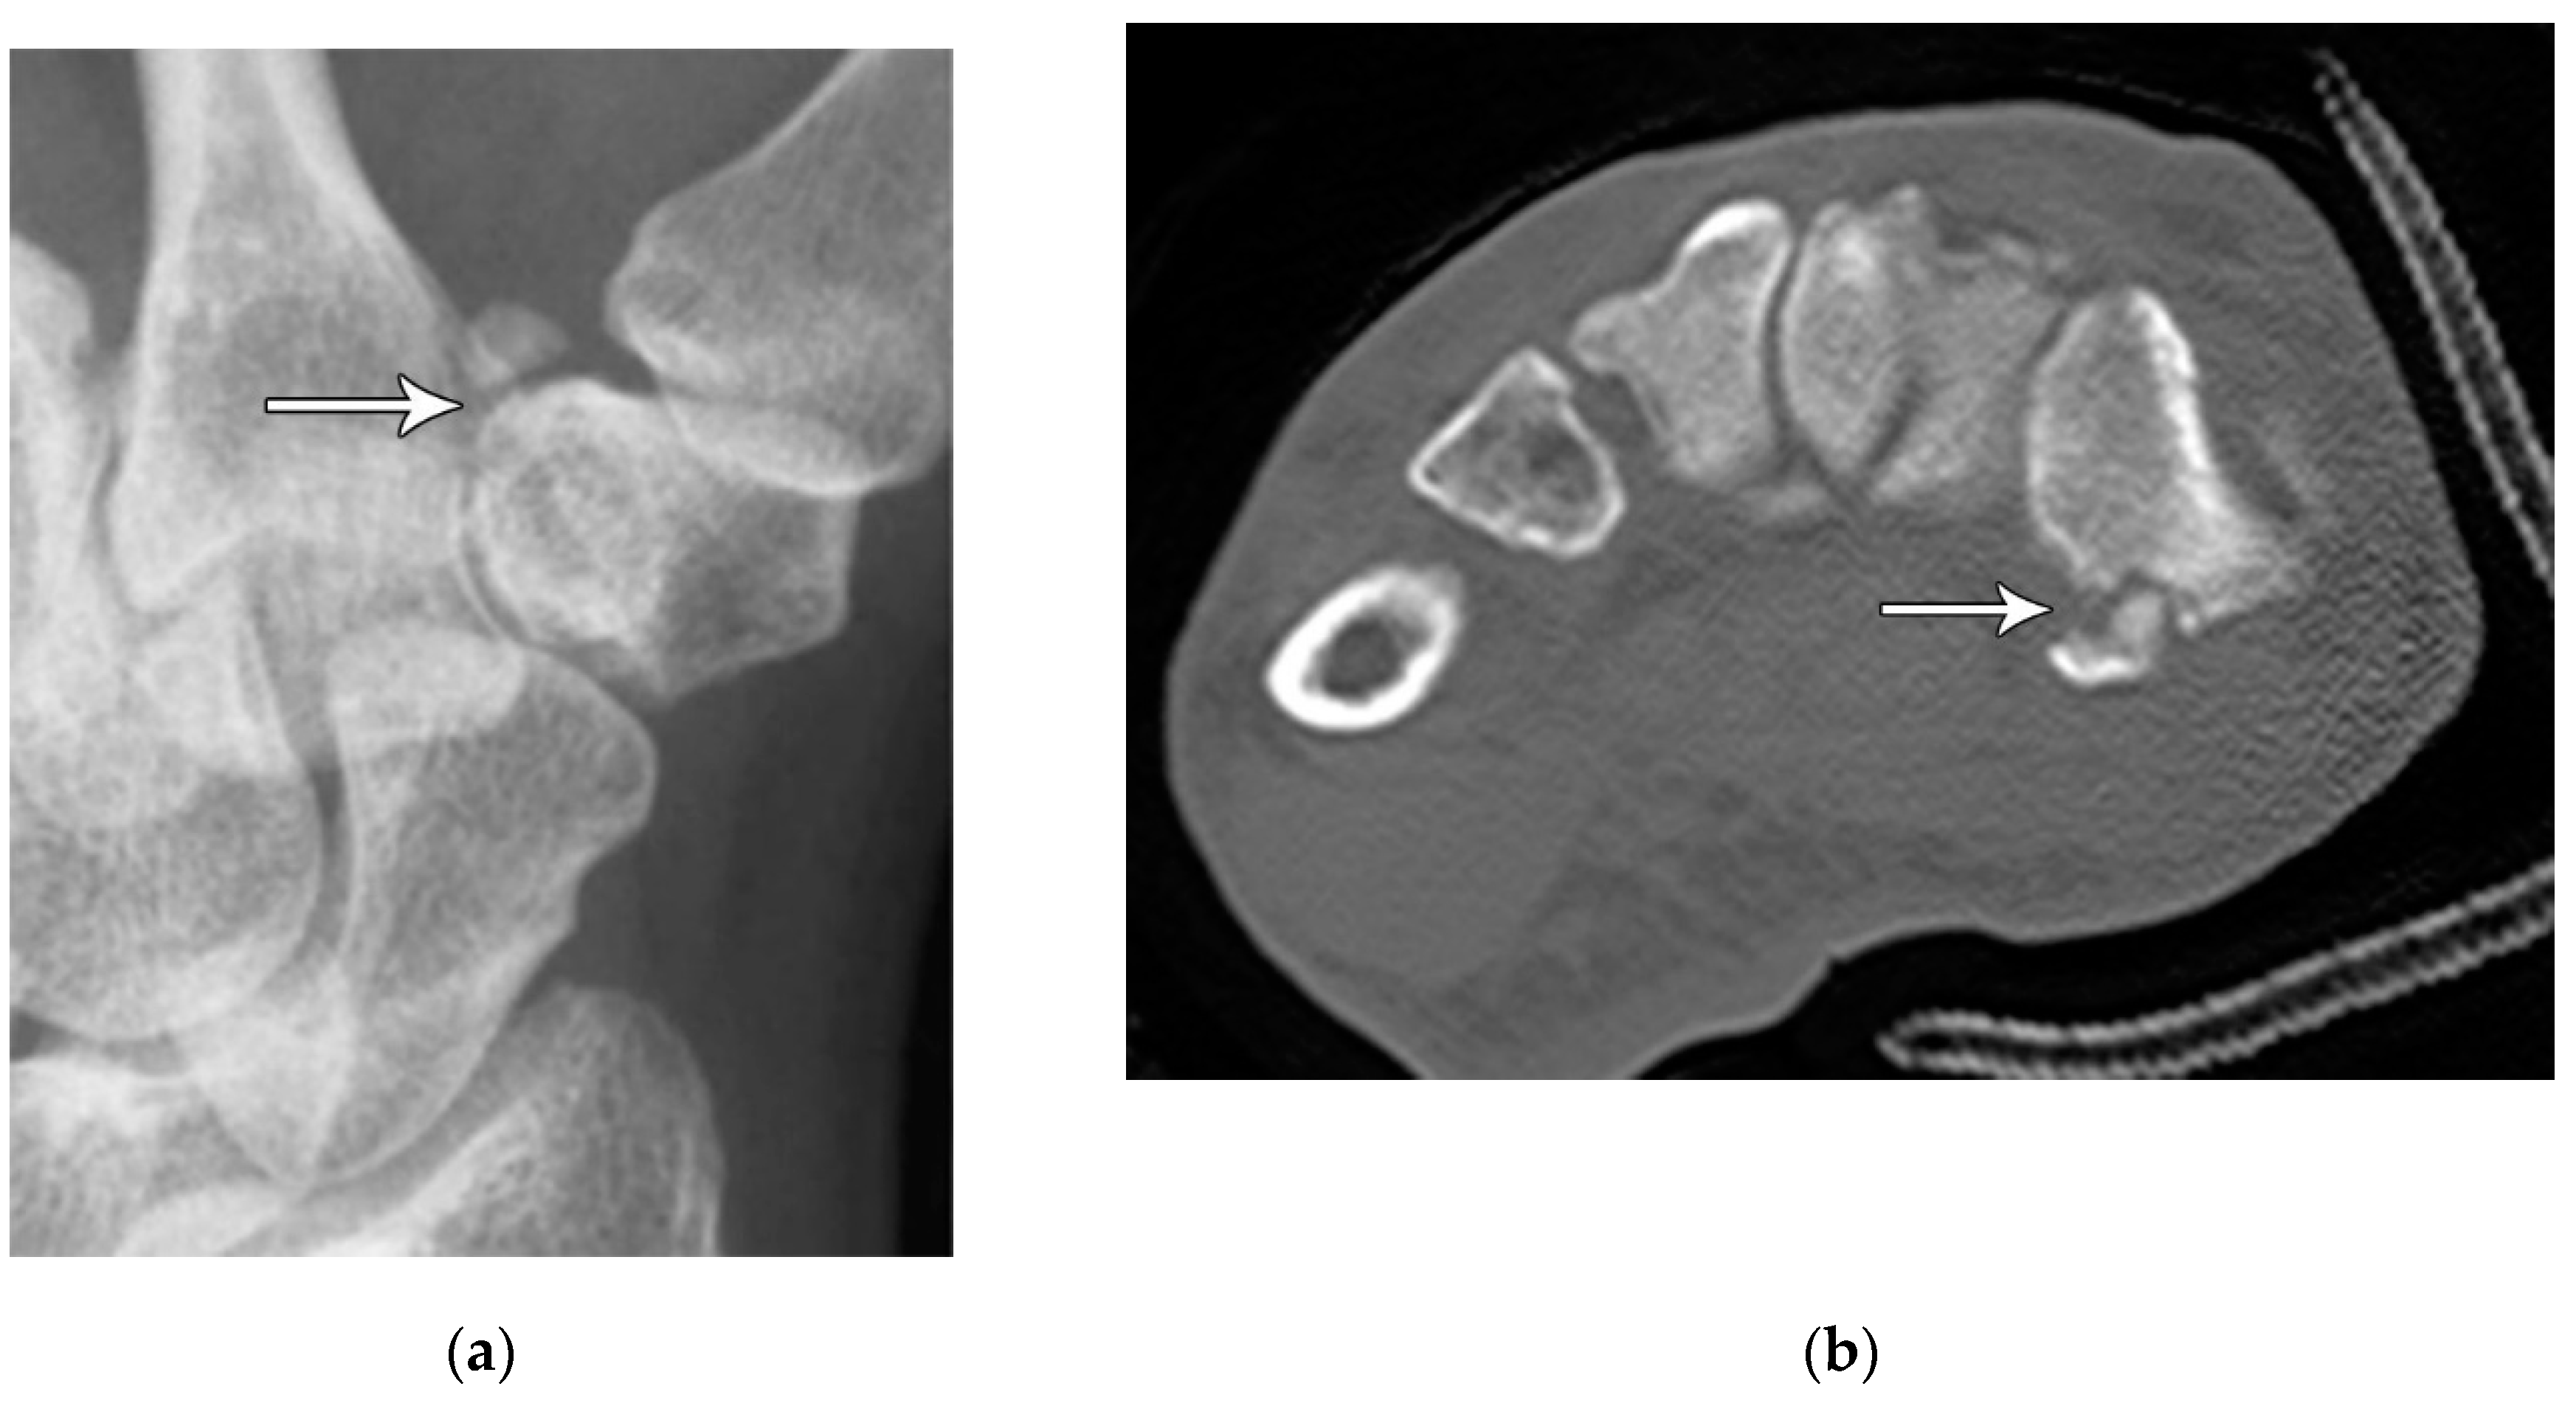

Figure 10. (a) PA radiograph of the wrist showing a triquetral body fracture (arrow) and concurrent scaphoid fracture (arrowhead). (b) Coronal reformatted CT confirms these findings with greater detail. (c) Lateral radiograph of the wrist showing a dorsal cortex fracture of the triquetrum with a tiny, avulsed fragment (curved arrow).